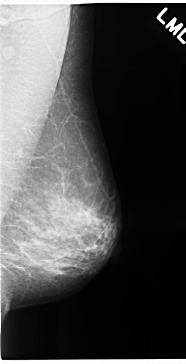

C_0115_1.RIGHT_MLO

RIGHT_MLO LINES 4680 PIXELS_PER_LINE 2496 BITS_PER_PIXEL 12 RESOLUTION 50 OVERLAY

FILE: C_0115_1.RIGHT_MLO.OVERLAY

TOTAL_ABNORMALITIES 1

ABNORMALITY 1

LESION_TYPE MASS SHAPE ROUND MARGINS SPICULATED

ASSESSMENT 5

SUBTLETY 5

PATHOLOGY MALIGNANT

TOTAL_OUTLINES 1